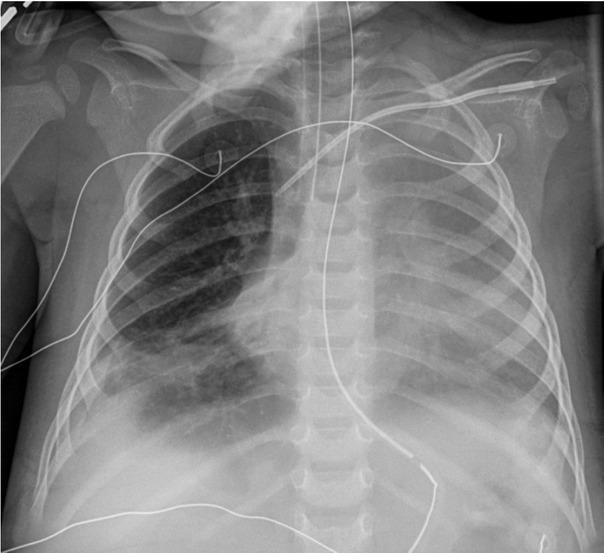

Fig. 2